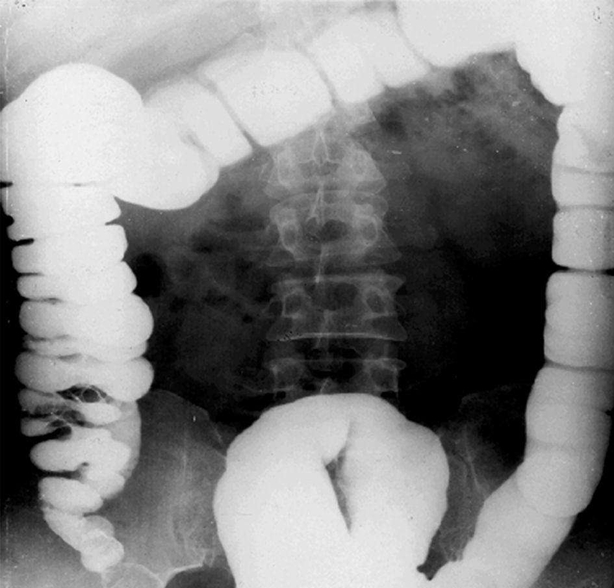

腸梗阻常見原因:動力性、麻痹性、痙攣性: 機械性(最為常見)、單純性(無血運障礙)、絞窄性(有血運障礙)、血運性(腸系膜動脈血栓)。

急性小腸梗阻:小腸擴張積氣,小腸腔內(nèi)積液,結(jié)腸內(nèi)氣體少。